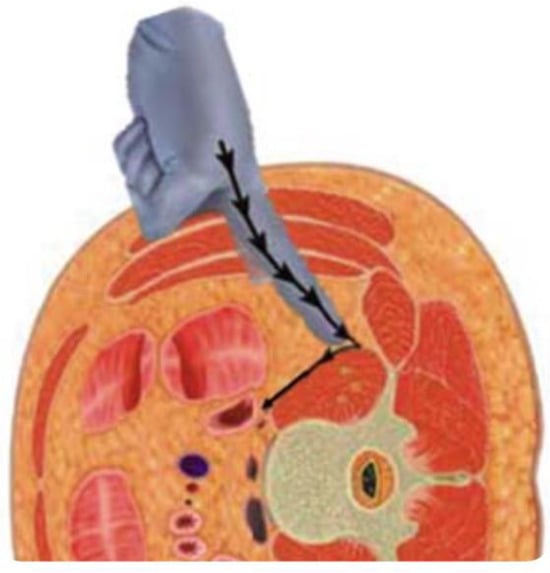

In physical therapy, it is necessary to identify the path of entry for spinal fusion and to understand the muscles involved [] (Figure 9). Muscle atrophy results from denervation due to surgical invasion of the multifidus and erector spinae muscles for posterior approach (PLIF and TLIF) [,]. LLIF incises the external oblique, internal oblique, and transversus abdominis muscles, resulting in post-operative muscle weakness (Figure 10). Hence, rehabilitation should be focused according to the procedure performed, as trunk extension and trunk flexion strength strongly correlate with ODI [].

Figure 10.

Oblique lumbar interbody fusion (OLIF) approach.

6.2. Psoas Muscle Strengthening

In XLIF, the disk space is approached through the psoas muscle. XLIF splits the psoas major muscle, resulting in muscle weakness at a rate of 9% to 31% []. OLIF avoids splitting of the psoas major muscle but is still associated with a 1.2% incidence of psoas muscle weakness []. Corrective spinal fusion for ASD with OLIF has also been shown to decrease psoas major muscle strength []. Strength of the psoas major muscle is related to post-operative gait sway after ASD correction [] and to the rate of bony fusion [], making post-operative strengthening of the psoas major muscle an important part of physical therapy programs.